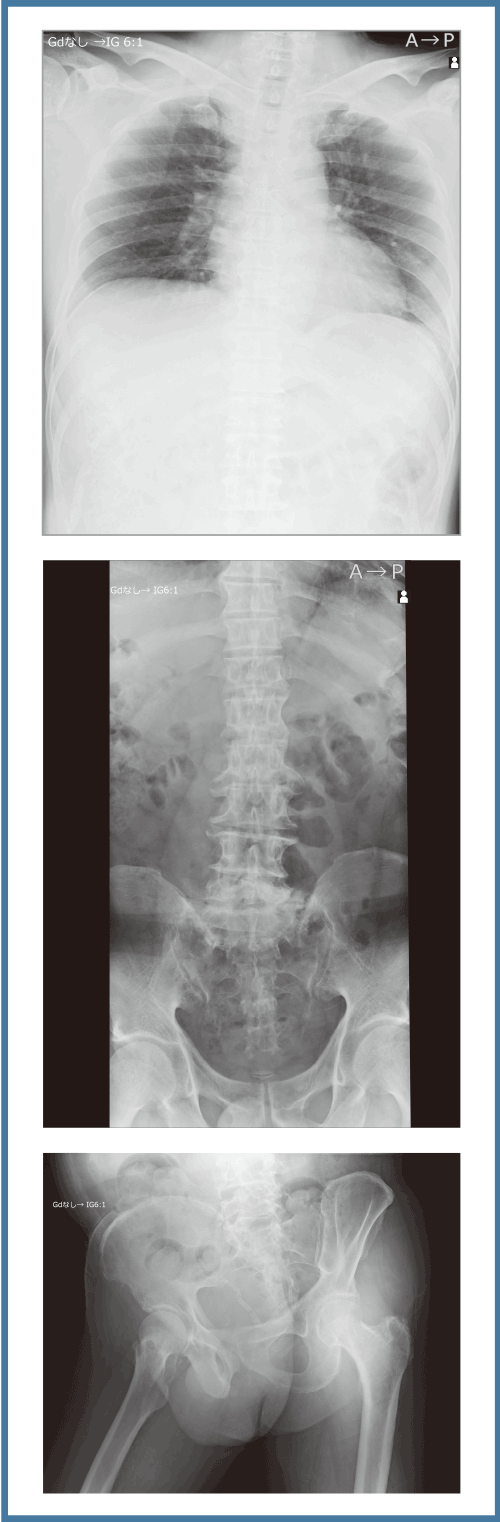

REALISM処理

Hybrid処理(従来処理)

画像全体の描出とコントラスト維持の両立

改良されたダイナミックレンジ圧縮の処理と、新規のLUT(階調カーブ)により、低線量域から高線量域まで各構造物を分離良く表現し、白トビ・黒ツブレを起こすことなく画像全体を自然なままに描出することで立体感のある画像を提供します。

被写体内のヒストグラム解析によりダイナミックレンジ圧縮の処理強度を自動で最適化する技術、「REALISM tune」を新たに搭載。 被写体厚によらず全関心領域を視認可能にし、撮影後の調整作業負担を軽減します。